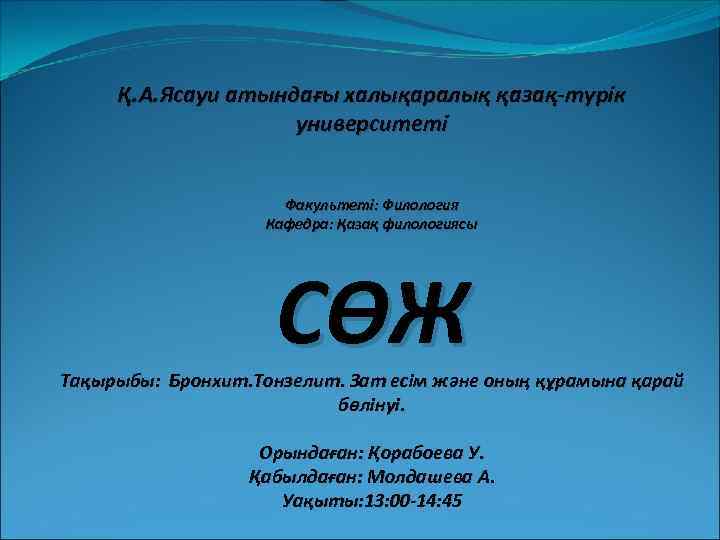

Бронхит Көмей Кеңірдек Басты бронхтар Плевра қуысы Париетальді плевра Висцеральді плевра Жүрек